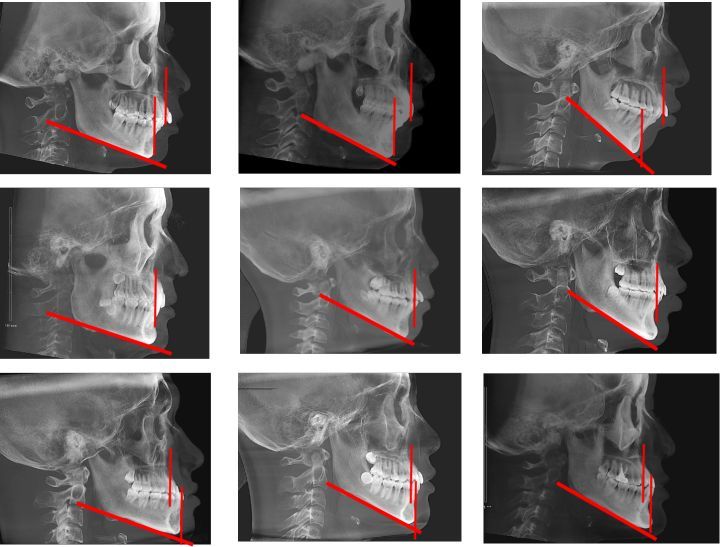

上颌前突

上颌前突病例一则

上颌前突能治愈么? - 知乎

主要通过移动构成我们面部最主要的两块骨骼——上颌骨和下颌骨,从而

也就是牙性前突的患者上颌骨是不突的,因此"牙性"前突中上前牙往前